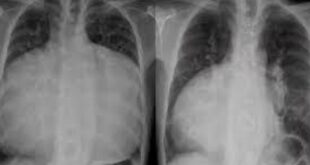

حالة نادرة… قلب رجل يملأ صدره بالكامل ! بعدما عانى الرجل من ضيق في التنفس استمر قرابة ستة أشهر شُخص رجل بحالة نادرة للغاية بعد أن وجد الأطباء أن قلبه قد تضخم لدرجة أنه ملأ تجويف صدره بالكامل، وفقاً لصحيفة «إندبندنت». وكتب الخبراء عن حالة الرجل في منتصف العمر المجهول …